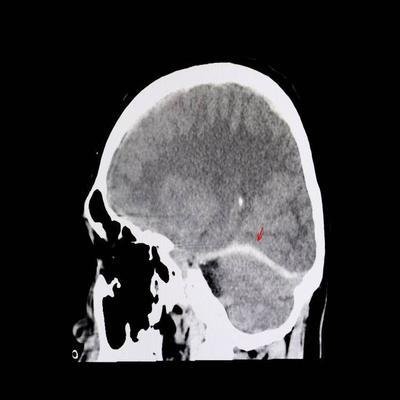

蛛网膜出血(SAH)是指大脑底部或者表面病变之后血管发生破裂,导致血液直接流入蛛网膜而引发的临床综合征。在临床上,蛛网膜出血还可被划分为外伤性(继发性)和非外伤性(自发性)两大类。其中,非外伤性蛛网膜出血属于常见且致命的疾病之一。常见病因有脑动脉畸形、动脉瘤、血液病等。该类疾病在年轻人中多发,且多在情绪激动或者疲劳的情况下急性发作。